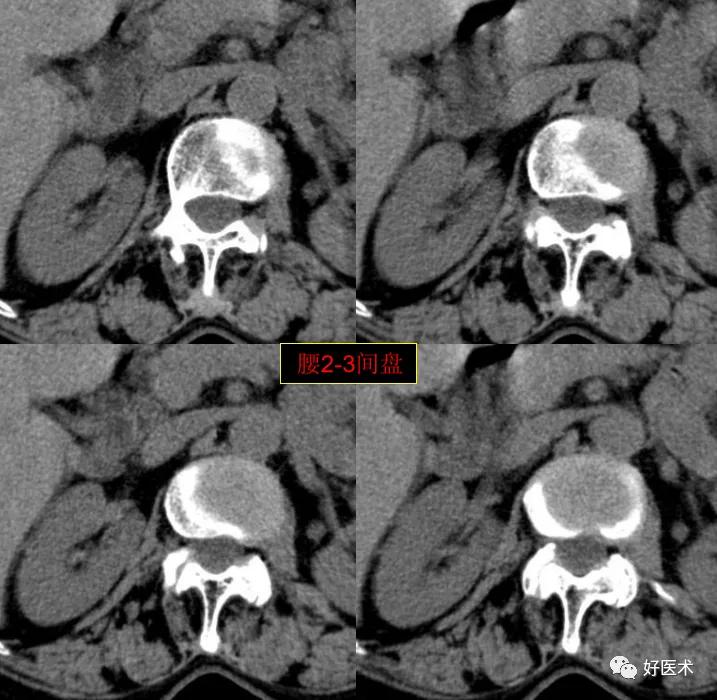

腰2-3间盘未见著变。

发现了什么?左侧竖脊肌较右侧明显肿胀饱满, 肌间脂肪间隙消失!!